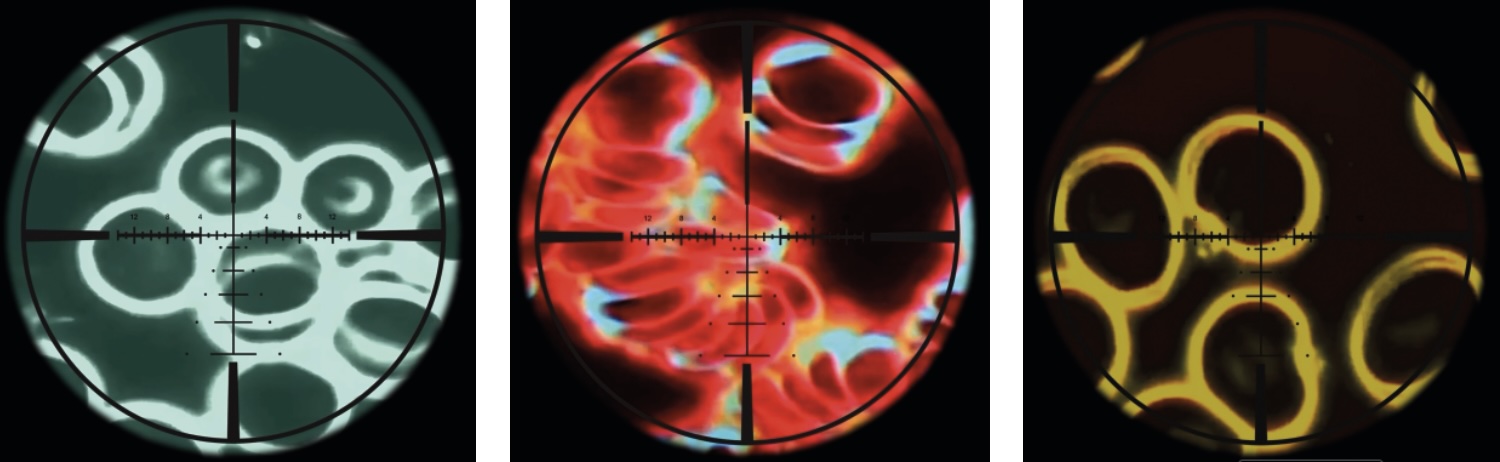

- Etude d'observation : tests in vivo sur globules rouges : pas d'effet d'agglutinement avec HSC 5G Smart Card. Pour ce test, le laboratoire compare une goutte de sang prélevée dans le doigt après une exposition aux ondes d'un smartphone sans protection d'une part (au centre), et avec protection HSC d'autre part (à droite). Les photos sont prises grâce à un microscope à fond noir (on peut voir les globules bouger). Sur la photo au centre, on peut observer des groupes de globules rouges denses, agglutinés et peu fluides, ce qui montre un signe de réponse immunitaire. L'effet ne se produit pas si l'appareil est protégé par HSC (à droite), ce qui montre que le corps n'a pas besoin de se défendre.